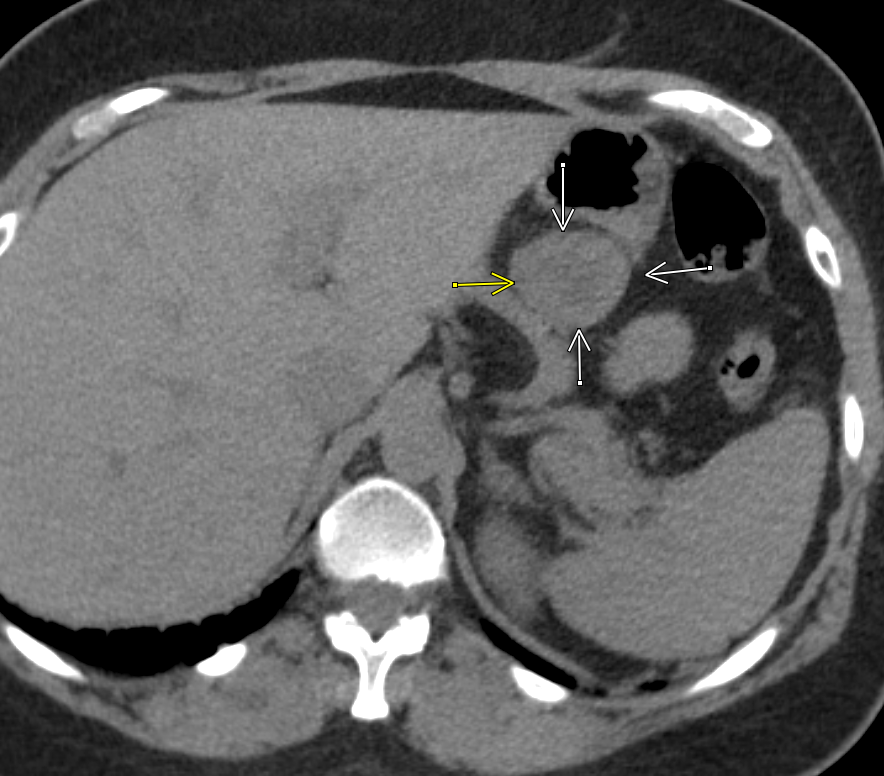

#easytomiss gastric stromal tumor on a ureter CT with no oral or intravenous contrast#radres look in all three planes before dismissing it as a bowel loop#radiology#EMRadpic.twitter.com/rwvrRbABRn